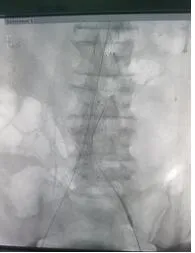

9月17日,乐鱼在线登录入口成功开展一例腹主动脉瘤覆膜支架腔内隔绝手术。患者术后恢复良好,此手术的开展标志着医院心脏外科微创治疗技术又上新台阶。9月16日,市中心医院胸心外科收治一名腹主动脉瘤患者。患者李某因胃部不适,在当地医院行常规体检时发现腹部搏动性包块,于西京医院完善主动脉CTA检查,提示腹主动脉瘤,建议行手术治疗。当患者得知乐鱼在线登录入口也能开展心脏大血管手术后,遂来就诊。

胸心外科姜永红副主任接诊该患者后,考虑患者病情危急,随时有腹主动脉瘤破裂危险,立即上报医务科,启动MDT团队。次日胸心外科团队在介入科及相关科室支持下成功完成医院首例腹主动脉瘤覆膜支架腔内隔绝术。

9月17日,手术顺利进行,李某身体内的“炸弹”危机随之解除,家人悬着的心也放下来了。姜永红介绍,主动脉瘤不是真正的动脉肿瘤,而是各种原因造成的主动脉局部或多处扩张,膨大呈瘤样改变称为主动脉瘤。主动脉瘤通常与老龄化、高血压、动脉粥样硬化、遗传、外伤、感染或其他损伤动脉壁强度的各种因素有关。日积月累,动脉壁日益薄弱,动脉瘤突然破裂可导致病人突然死亡。